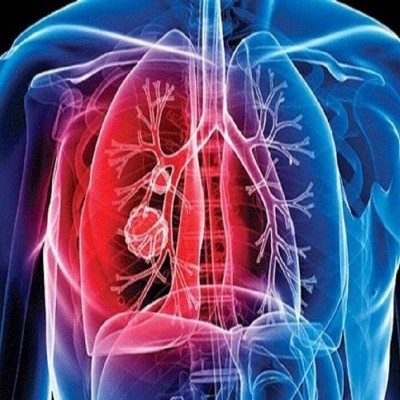

غربالگری، کلید شناسایی زودهنگام سرطان پیشرفتهای درمان سرطان و امید به درمان قطعی در مراحل اولیه/ افزایش سن جمعیت و پیشرفت ابزارهای تشخیص؛ دو عامل افزایش آمار سرطان